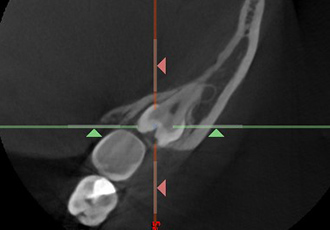

高精度な矯正治療には、治療技術だけでなく精密な検査や分析が必要不可欠です。当院では、歯の移動に関する口腔内の3次元情報を採取する歯科用CTや、事前にシミュレーションすることができる口腔内スキャナー(iTero)などといった専門的なデジタル設備を導入しております。

CT検査によって取得した口腔内の3Dデータから、歯の位置や埋伏歯(歯冠の全てまたは一部が埋まって出ていない歯)・過剰歯(決まった本数よりも多く生えている歯)などを確認します。

これらを事前に確認しておくことで、歯が移動する際に邪魔になってしまうのを防ぎます。また、歯の移動に大きく関係する骨の厚さなどの情報も得られ、精度の高い矯正治療のために不可欠な検査です。

CT検査を行うことで、さまざまな角度の断面から

歯の位置や方向を確認することができます。

アキシャル像

コロナル像

サジタル像

※症例に合わせて必要な場合にのみCT検査を行います。